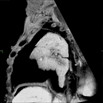

Caption Play MovieSerial 2D EFIC image stack in the coronal plane of 2404-002-3 (E15.5) reveals DORV and AVSD

Copyright This image is from the Laboratory of Dr. Cecilia Lo, a member of the Cardiovascular Development Consortium (CvDC), Bench to Bassinet (B2B) program of the National Heart Lung and Blood Institute (NHLBI), and is displayed with the permission of the authors. J:175213

Qrich1b2b2404Clo glutamine-rich 1; Bench to Bassinet Program (B2B/CVDC), mutation 2404 Cecilia Lo

Qrich1b2b2404Clo/Qrich1b2b2404Clo C57BL/6J-Qrich1b2b2404Clo